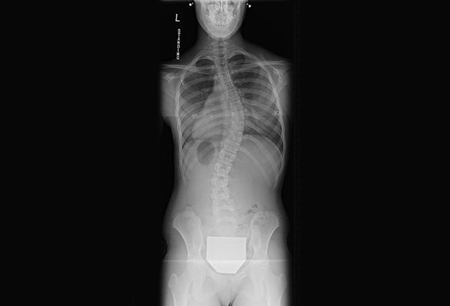

Posteroanterior scoliosis radiograph of a 13-year-old girl with a 49° right thoracic curvature with apex at the T9-T10 disc space

From the collection of Stuart Weinstein, MD, University of Iowa; used with permission